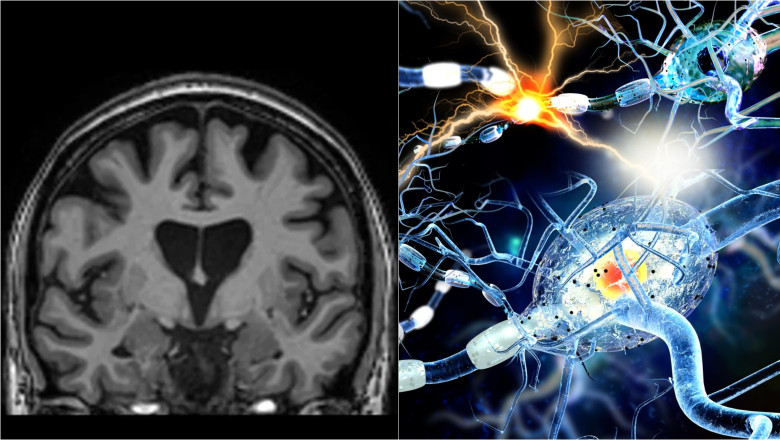

Tratamentul presupune introducerea în creier a unui virus inofensiv, care a fost modificat genetic pentru a conține o anumită secvență de ADN, printr-o intervenție chirurgicală delicată care durează între 12 și 18 ore, potrivit BBC.

Virusul acționează apoi ca un poștaș microscopic care livrează acea secvență de ADN special concepută în interiorul neuronilor, acolo unde se activează.

Acest proces transformă practic neuronii într-o fabrică ce produce terapia care le va preveni moartea. Celulele produc apoi molecula micro-ARN (AMT-130) menită să intercepteze și să dezactiveze instrucțiunile trimise de ADN-ul celulelor pentru producerea proteinei huntingtin.